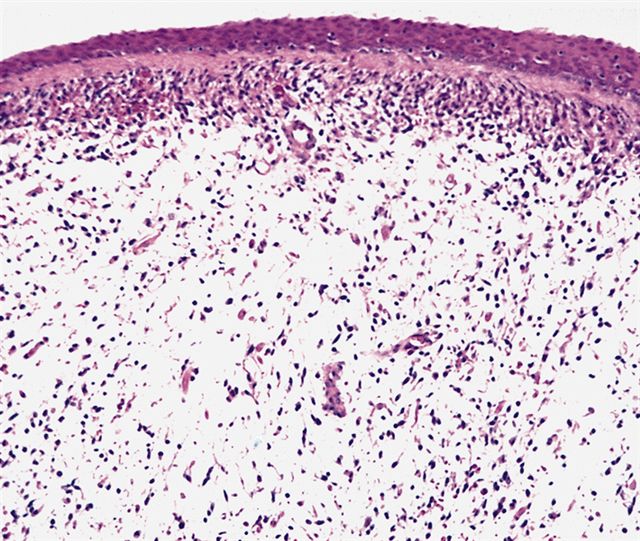

- Botryoid variant frequently shows a cambium layer: a hypercellular zone immediately beneath the epithelial surface

- Cells are undifferentiated, round or spindled with minimal cytoplasm, frequent mitotic figures

- Deeper layers of the tumor are typically less cellular but overall conform to the histology of embryonal rhabdomyosarcoma (ERMS) with variation by region

Microscopic (histologic) images

Contributed by Erdener Özer, M.D., Ph.D. and Mark R. Wick, M.D.

Contributed by Carolina Martinez Ciarpaglini, M.D., Ph.D. (Case #276) - tonsillar mass

AFIP images - botryoid variant